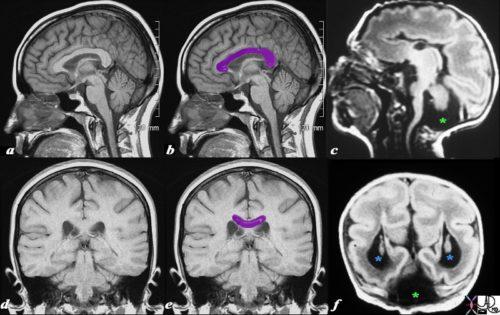

Достоверным методом, позволяющим с высокой степенью точности провести диагностику, является магнитно-резонансная томография (МРТ). Благодаря исследованию выявляются:

- наличие кистозных новообразований в черепной ямке;

- аномальное развитие мозжечка;

- расширение четвертого желудочка;

- водянка мозга.